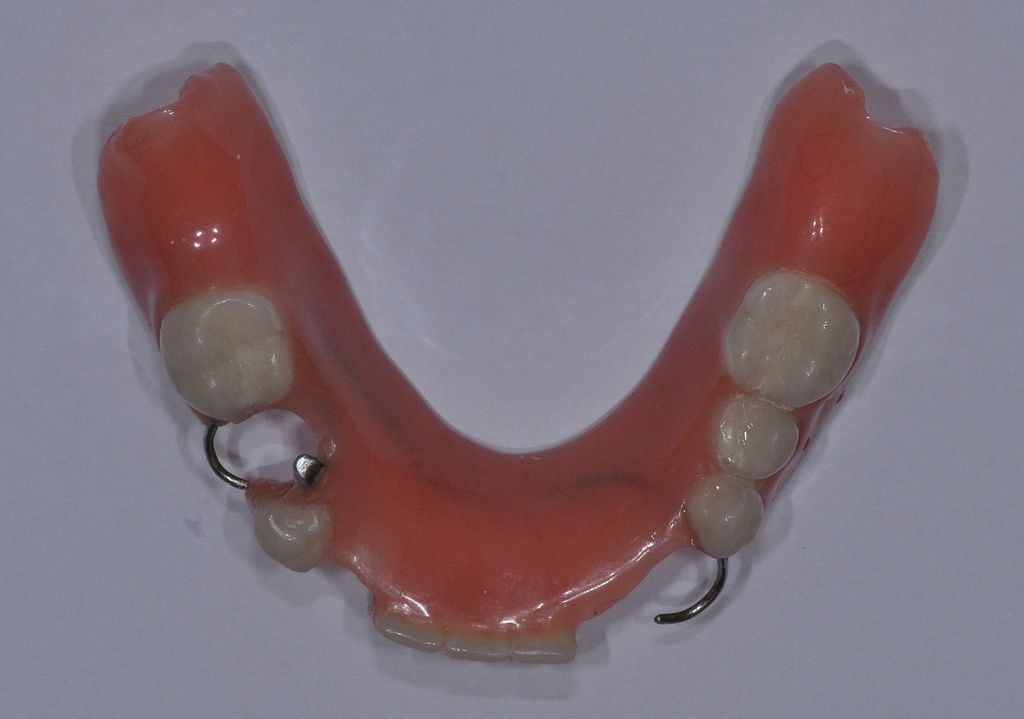

一個功能正常設計良好的

活動假牙,會透過一些假牙上的設計,或零件與嘴巴裡剩下的牙齒或植牙來固定,最常見的方式就是鉤子。透過這些方式來固定後,使用活動假牙來吃東西時在口內是穩定狀態,但是在休息或清潔的時候,病人可以將活動假牙自己從嘴巴取下來做清潔的動作,所以活動假牙不是吃東西的時候會動來動去,而是指病人可以在需要的時候自由取下。